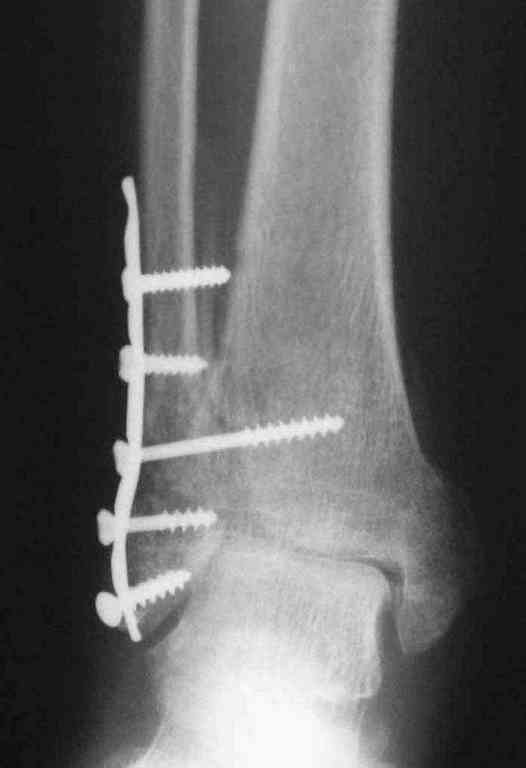

Второй снимок через 3 месяца после реконструктивной операции.

Вторая пациентка 34 лет, перелом получала в Испании, где от операции отказалась, дома по приезду сняла скотчкаст и лечилась у костоправов, нагрузка с 3 недели. Операция через 3 мес после травмы. Остеотомия м-б кости, фиксация пластиной, восстановление МБС. Так как медиальная лодыжка подтянулась, суставная щель на ЭОП контроле нормализовалась ограничились латеральным доступом. Реконструкцию заднего края не пытались сделать тк там уже прослеживалась консолидация, а сминать эпиметафиз не хотелось. В настоящее время ходит с тростью \три месяца после операции\, сустав нестабилен-слабость дельтовидной связки. Супинатор и плотные кроссовки дают возможность длительно ходить.

Первый снимок сделан в Испании после репозиции, второй через 2 месяца после травмы перед операцией, третий-через 3 мес после операции.